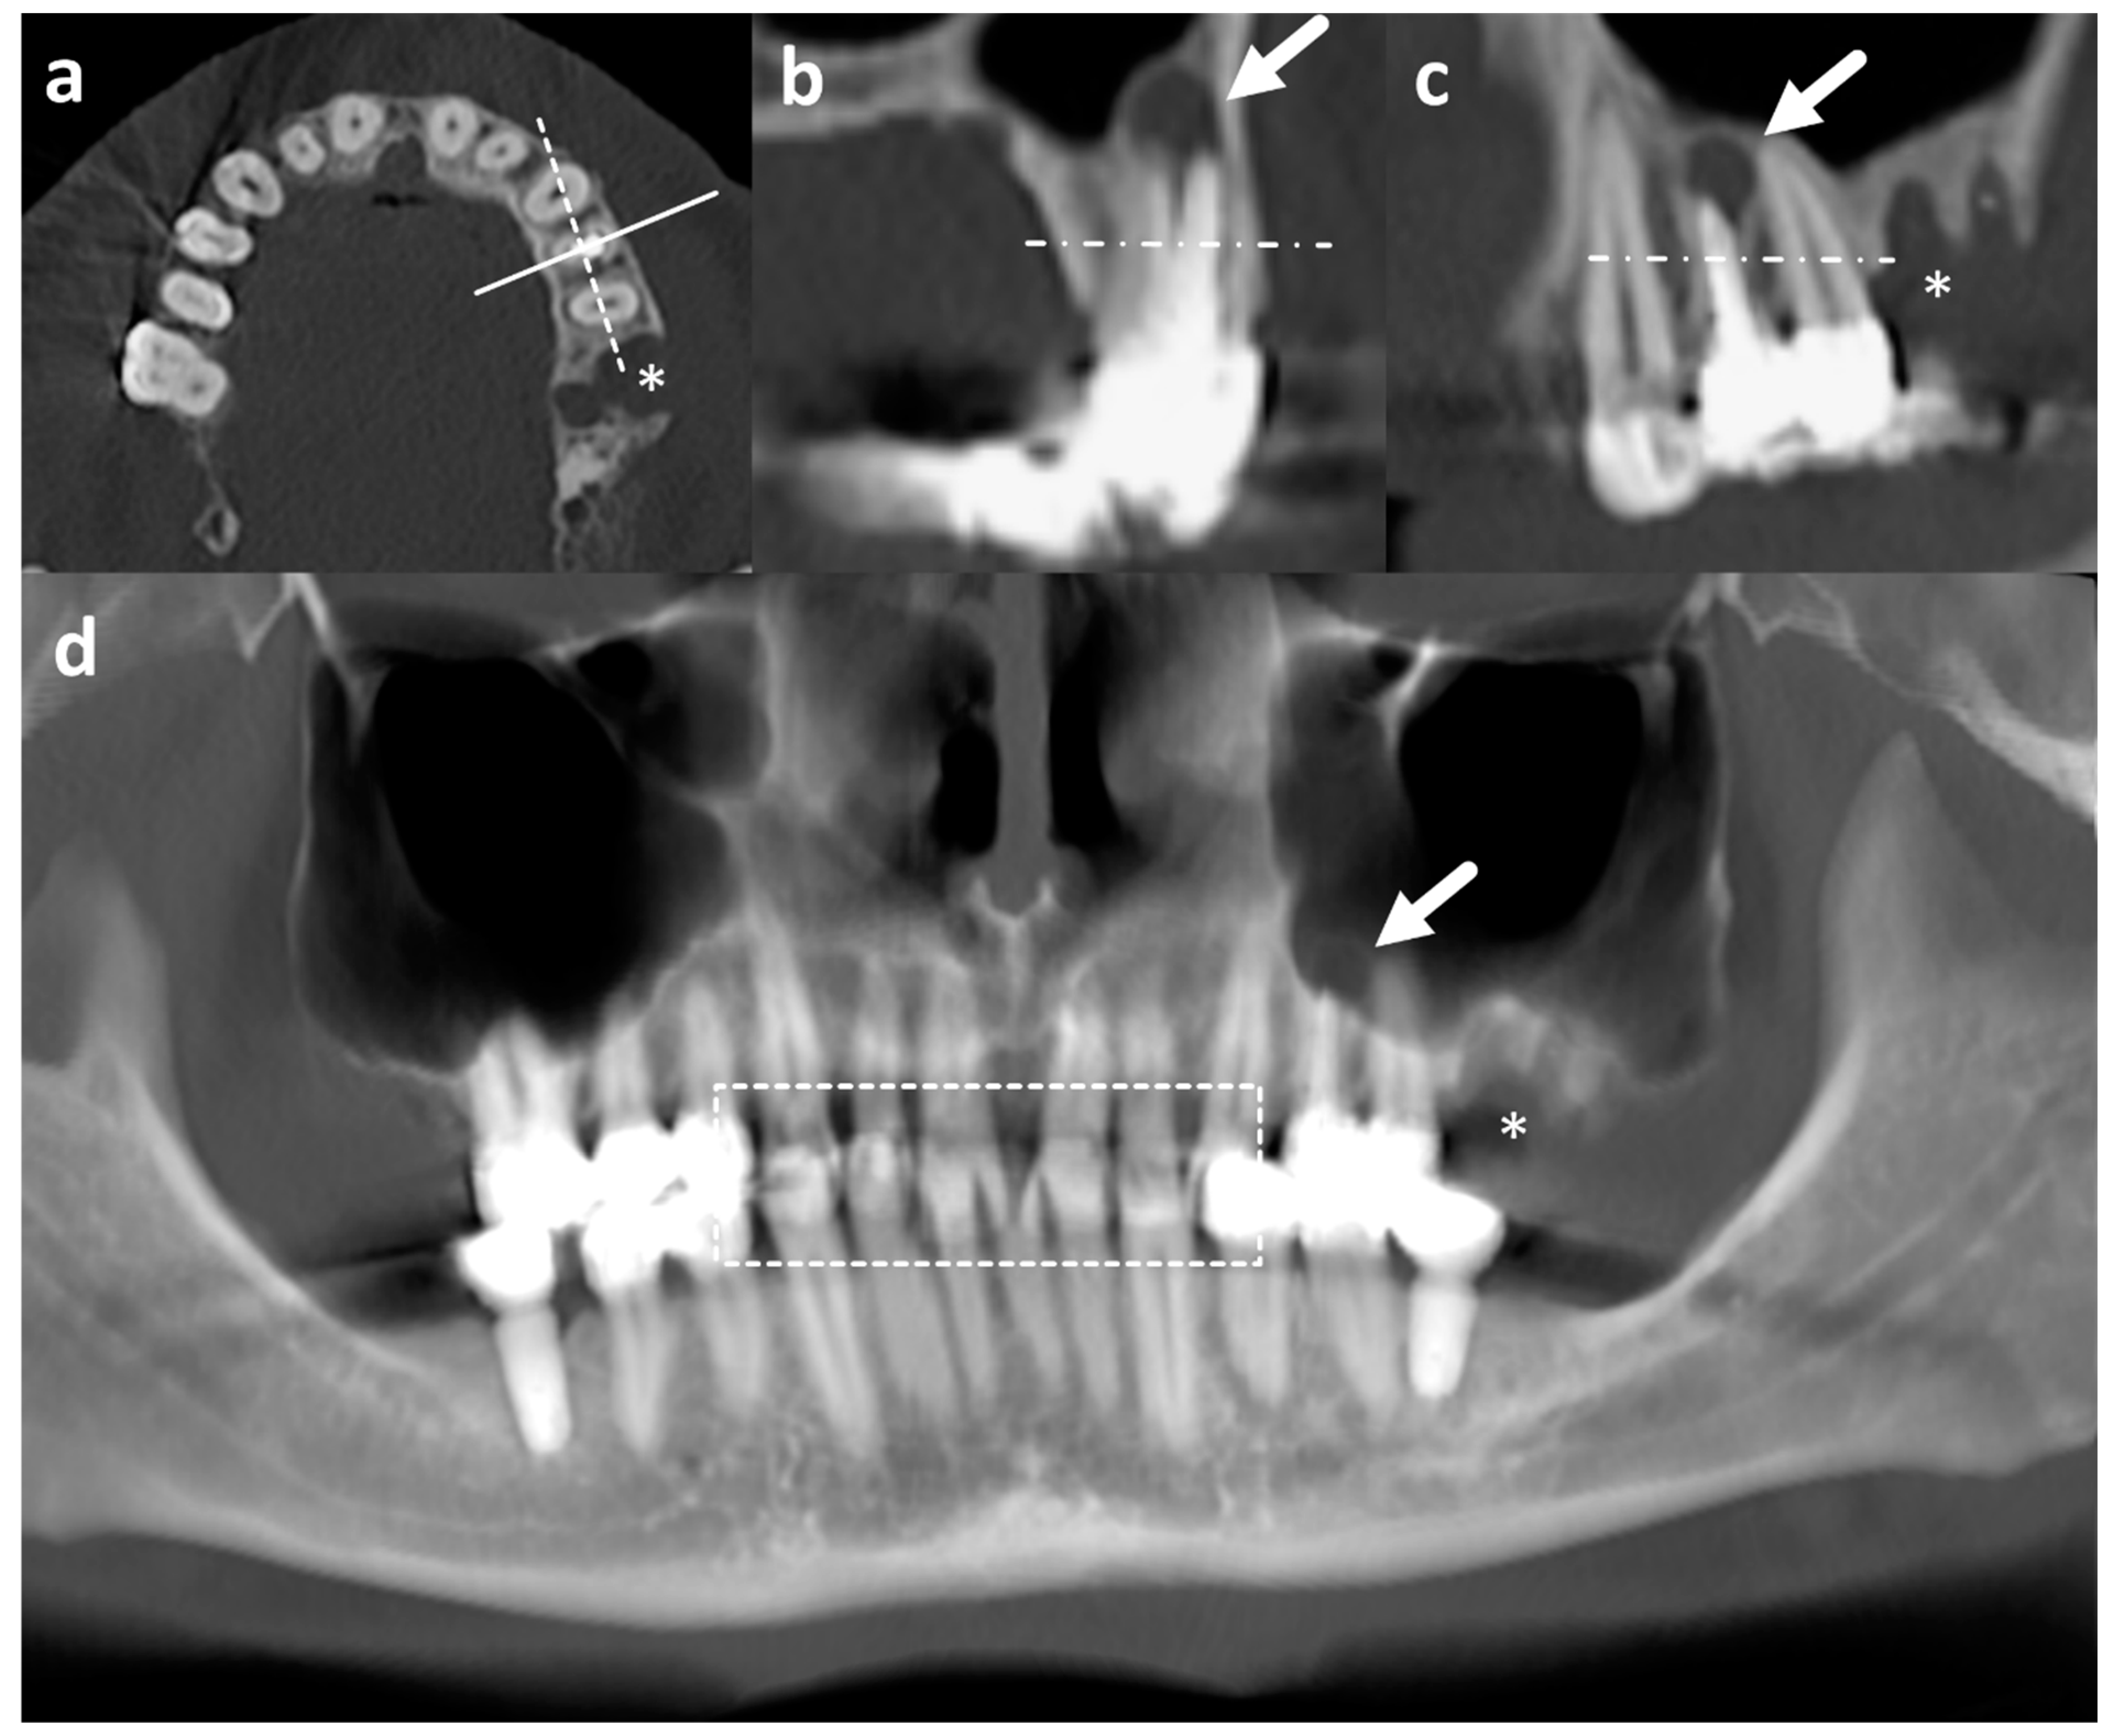

Figure 3.

Dental part of CT images in axial (a), sagittal (b), and coronal plane (c), and vOPG (d) of the same patient. The solid and dashed line in a corresponds to the plane of sagittal (b) and coronal (c) reconstructions reconstructed in 1 mm slice thickness, respectively. Note the periapical abscess at the left maxillary first premolar with root canal treatment (arrow in (b–d)) is much more conspicuous on CT than vOPG. The asterisk (*) marks a defect after tooth extraction (a,c,d). The dashed box in d contains areas of overlap due to closed jaws during examination impairing evaluability particularly of vOPG. Horizontal streak artefacts may be noted in all reconstructions parallel to the image acquisition plane in all reconstruction resulting from metal implants. CT = computed tomography examination; vOPG = virtual orthopantomogram.

All CT and vOPG exams were evaluated by one calibrated dentist on calibrated diagnostic monitors between November 2020 and February 2021. For evaluation of CT, all planes (axial, sagittal, and coronal, Figure 3a–c) were considered. The evaluation of the images lasted on average 20 min (CT) and ten minutes (vOPG), respectively.